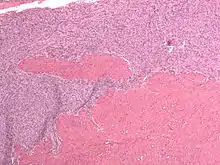

| Micrograph of a low-grade endometrial stromal sarcoma. H&E stain. | |

Low-grade endometrial stromal sarcoma consists of cells resembling normal proliferative phase endometrium, but with infiltration or vascular invasion. These behave less[3] aggressively, sometimes metastasizing, with cancer stage the best predictor of survival. The cells express estrogen/progesterone-receptors.

- Monotonous ovoid cells to spindly cells with minimal cytoplasm.

- Prominent arterioles. Angiolymphatic invasion common.

- Tongue-like infiltration between muscle bundles of myometrium.